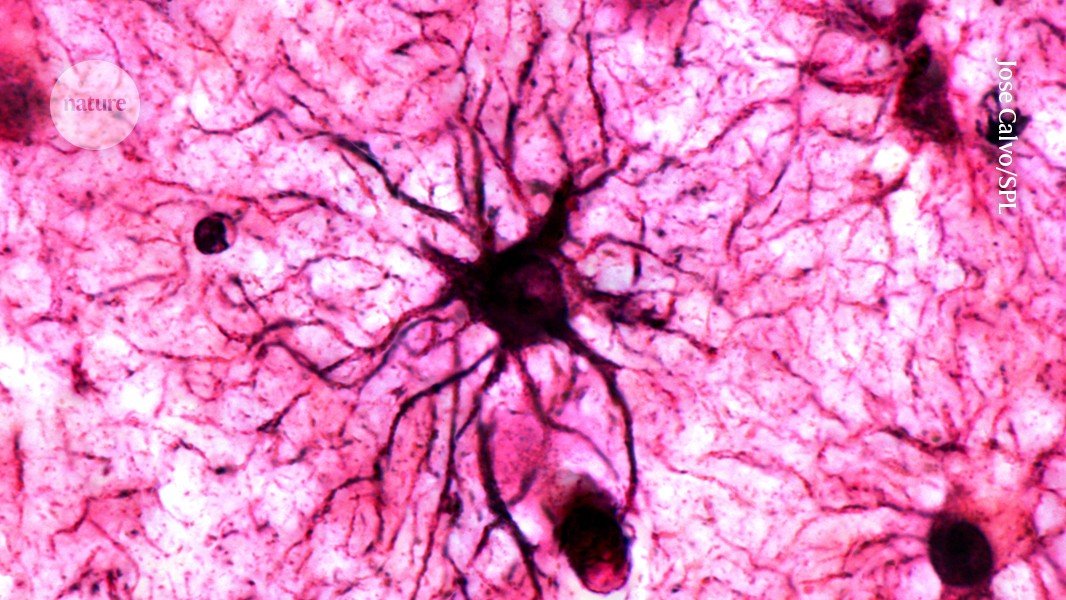

A type of brain cell called astrocytes play a crucial role in stabilizing memories in the brain.Credit: Jose Calvo/SPL

يلعب نوع من خلايا الدماغ يسمى الخلايا النجمية دورًا حاسمًا في تثبيت الذكريات في الدماغ.الائتمان: خوسيه كالفو / SPL